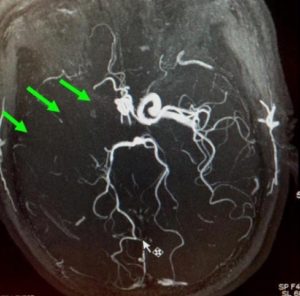

羅先生被送往私家醫院的第一步是進行緊急磁力共振造影,報告顯示羅先生右邊頸和腦部血管大動脈全部都被血栓堵塞着,右邊大腦缺血水腫,導致左邊手腳冇力和神智半昏迷。經過腦血管外科醫生的診斷和急救,在全身麻醉下,醫生使用尤如髪絲微細的導管,經過病人右邊大腿的腹股溝的大動脈而入,導管再經過腹部和胸腔的大動脈一直向上,遊走到病人右邊的頸和腦部血管大動脈,進行機械式血栓吸取內血管治療急救。

經過1小時的血管急救,所有血栓都被移除,羅先生的右頸和腦部血管都給順利打通,腦部缺血情況立即得到改善。血栓被吸取後, 腦血管外科醫生發現羅先生的右頸內動脈有嚴重血管狹窄的情況,這個狹窄就是羅先生中風的主要原因。醫生因此植入血管支架來重新擴張狹窄的血管,以防止羅先生將來中風復發。全身麻醉清醒後,羅先生的大腦意識和手腳活動能力即時好轉,他其後再被送回另一間公立醫院繼續康復治療。

| 導管遊走到病人右邊的頸和腦部血管大動脈,進行機械式血栓吸取 | |